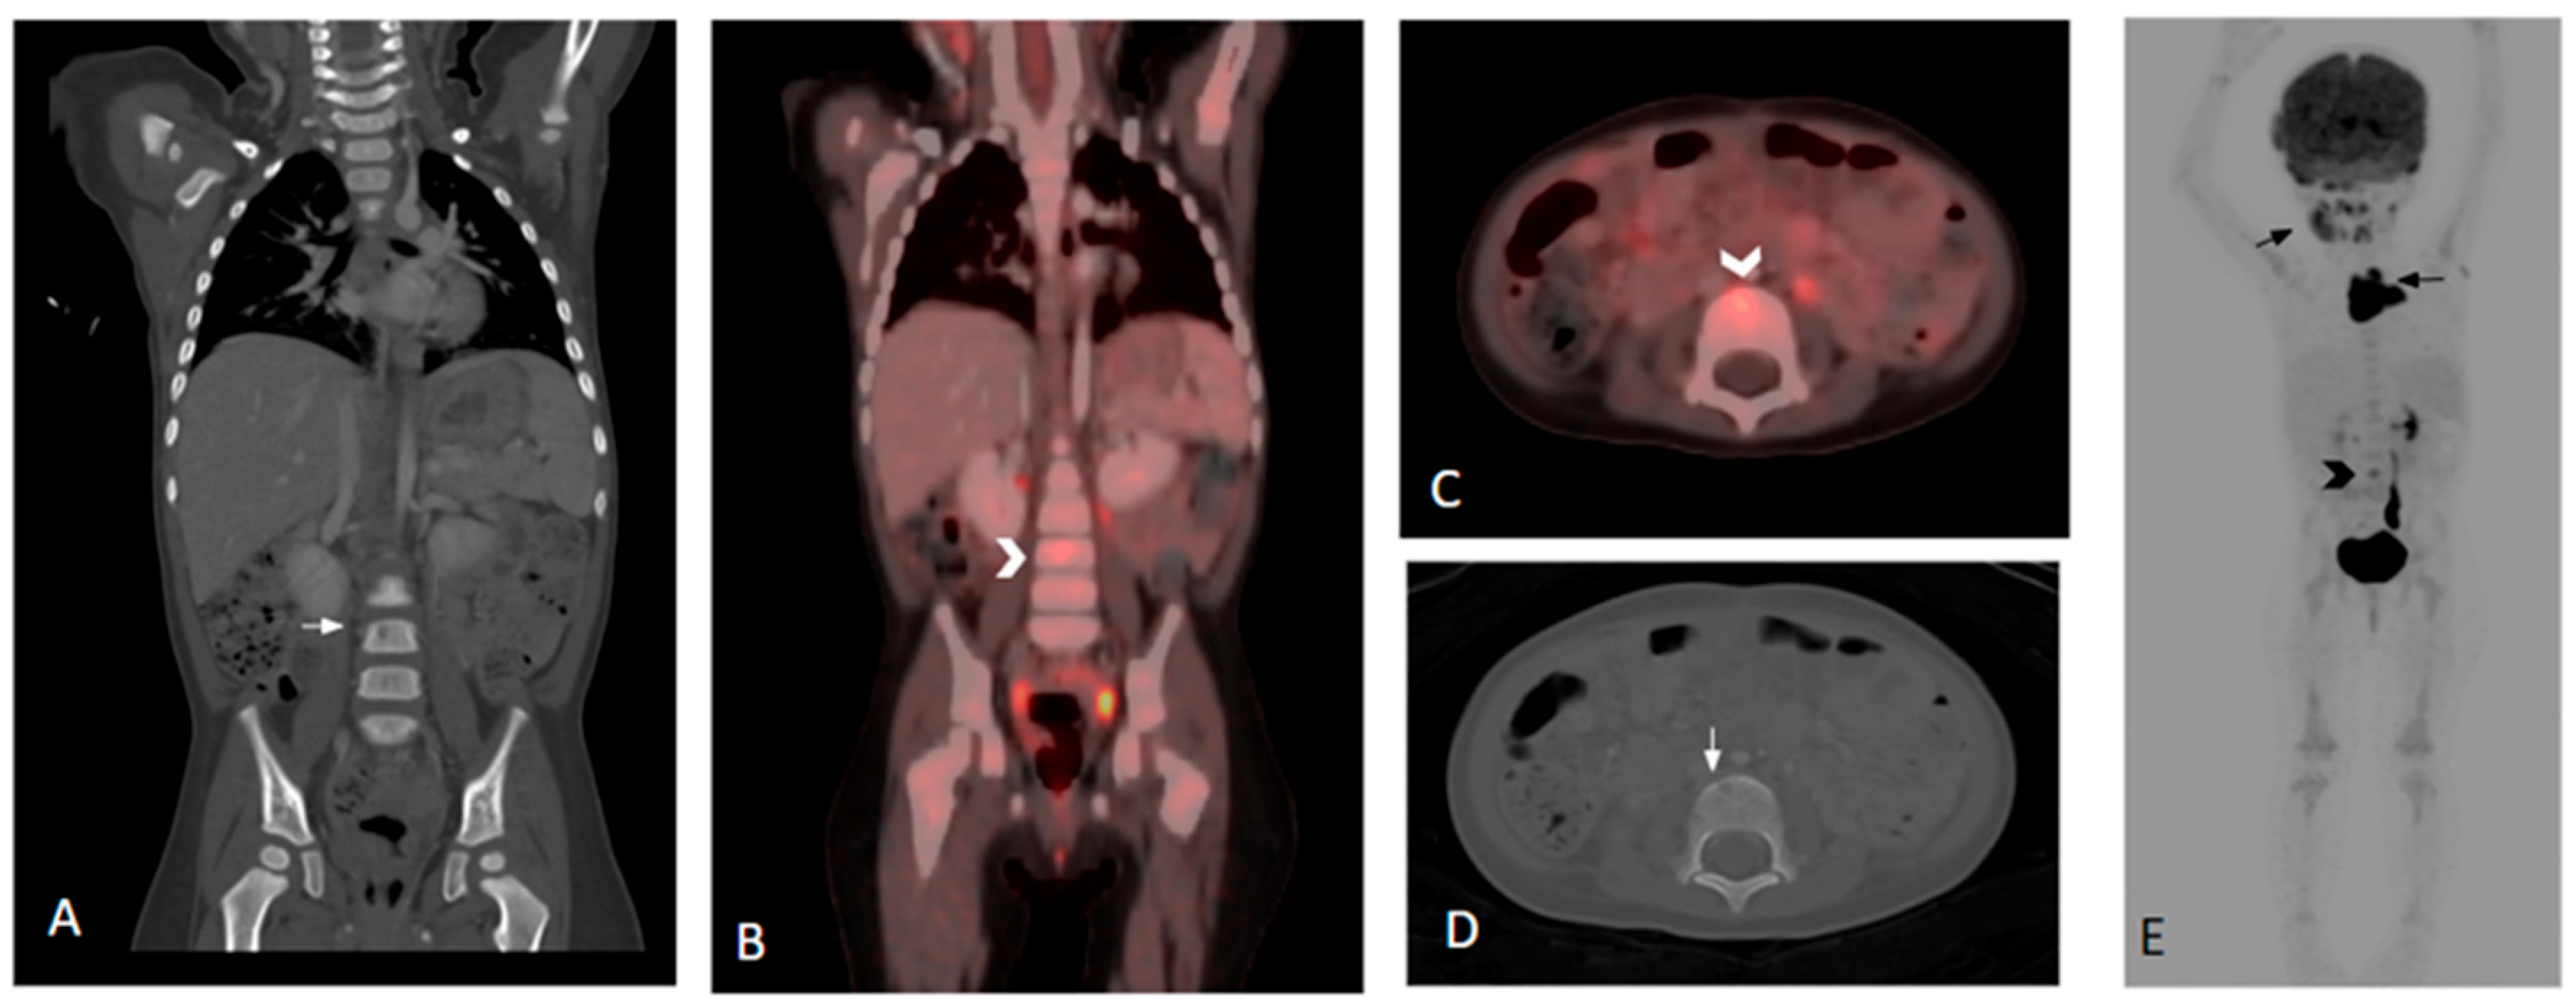

3.1.1. Identification of LCH Lesions at Diagnosis by PET Scans

3.1.2. Re-Staging or Assessment of Disease Reactivation by PET Scans

3.1.3. Assessment of Response to Therapy by PET Scans